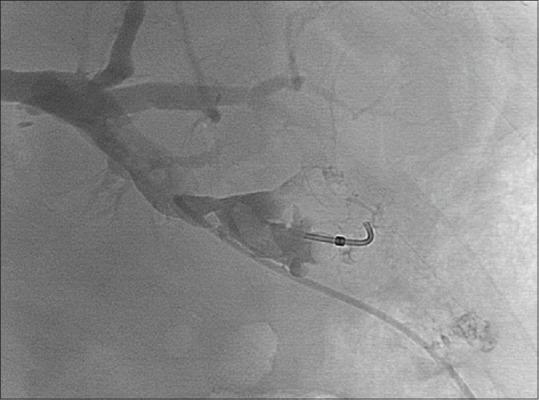

用氰基丙烯酸正丁酯闭塞胆皮瘘

Bilio-cutaneous fistula obliteration with NBCA.

Biliary fistula and bile leakage are complications that can occur during hepato-biliary surgery (both open and laparoscopic) and percutaneous biliary intervention. In some cases, spontaneous resolution is documented but more often re-intervention (surgical or percutaneous) is necessary. We present the case of a male patient who underwent right hepatectomy with bilio-digestive anastomosis for a cholangiocarcinoma which developed a bilo-cutaneous fistula through the path of a previously inserted percutaneous transhepatic drainage. Sealing of bilo-cutaneous fistula was obtained using N-butil-Cyanoacrylate. This technique has already been reported in some papers as a useful tool for biliary tree obliteration; however, to our knowledge, no cases describing the use of glue to seal a sub-cutaneous route are available in literature.

摘要

胆瘘和胆汁渗漏是肝胆手术(包括开腹手术和腹腔镜手术)及经皮胆道介入治疗过程中可能出现的并发症。在某些情况下,有自发缓解的记录,但更常见的是需要再次干预(手术或经皮介入)。我们报告一例男性患者,该患者因胆管癌接受了右肝切除术并进行了胆肠吻合术,术后通过先前插入的经皮经肝引流通道形成了胆皮瘘。使用N-丁基-氰基丙烯酸酯封闭了胆皮瘘。该技术在一些文献中已有报道,是用于闭塞胆道树的一种有用工具;然而,据我们所知,文献中尚无使用胶水封闭皮下通道的病例。